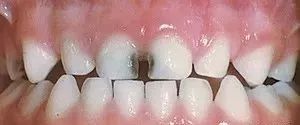

像这样的乳白色,这是虫牙开始的早期标志之一!!一定要注意观察,看孩子有没有这个特征。

A图:重度蛀牙

B图:靠近牙龈的地方有白色斑块,是蛀牙早期表现,说明牙齿开始慢慢脱框